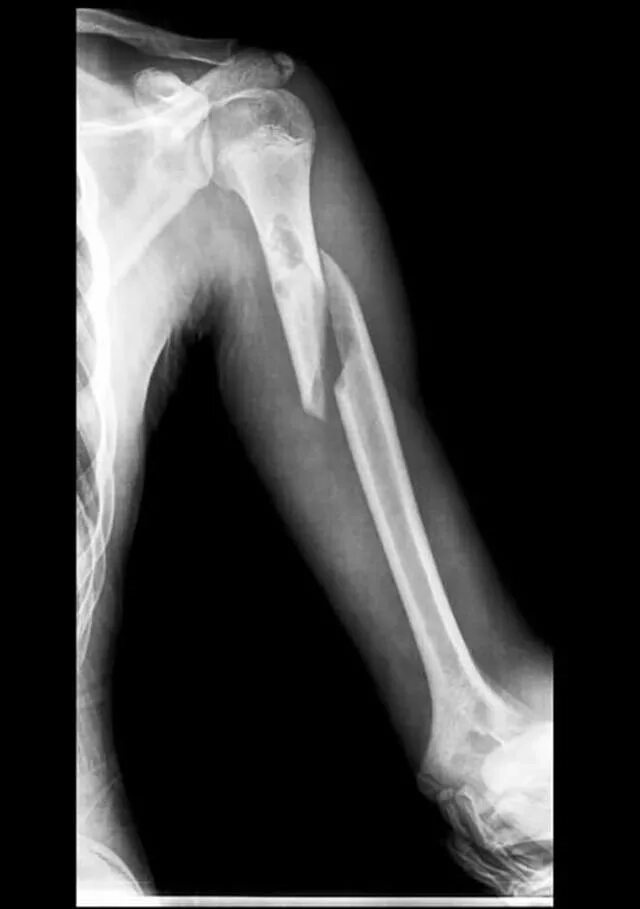

Закрытый оскольчатый перелом со смещением